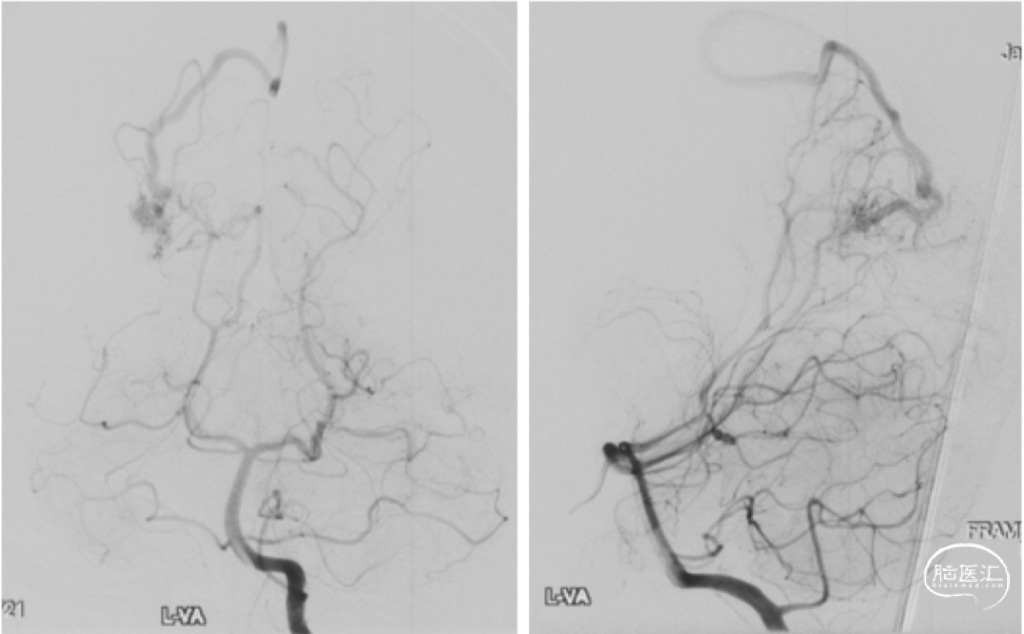

颅脑DSA

1个月后行DSA;左椎动脉造影提示右枕叶AVM(红色箭头),早显的皮层静脉(蓝色箭头)向上矢状窦引流。

复查DSA:AVM切除术后即刻复查造影,显示AVM切除完整,无异常早显引流静脉

切除术中造影显示动静脉畸形切除完全